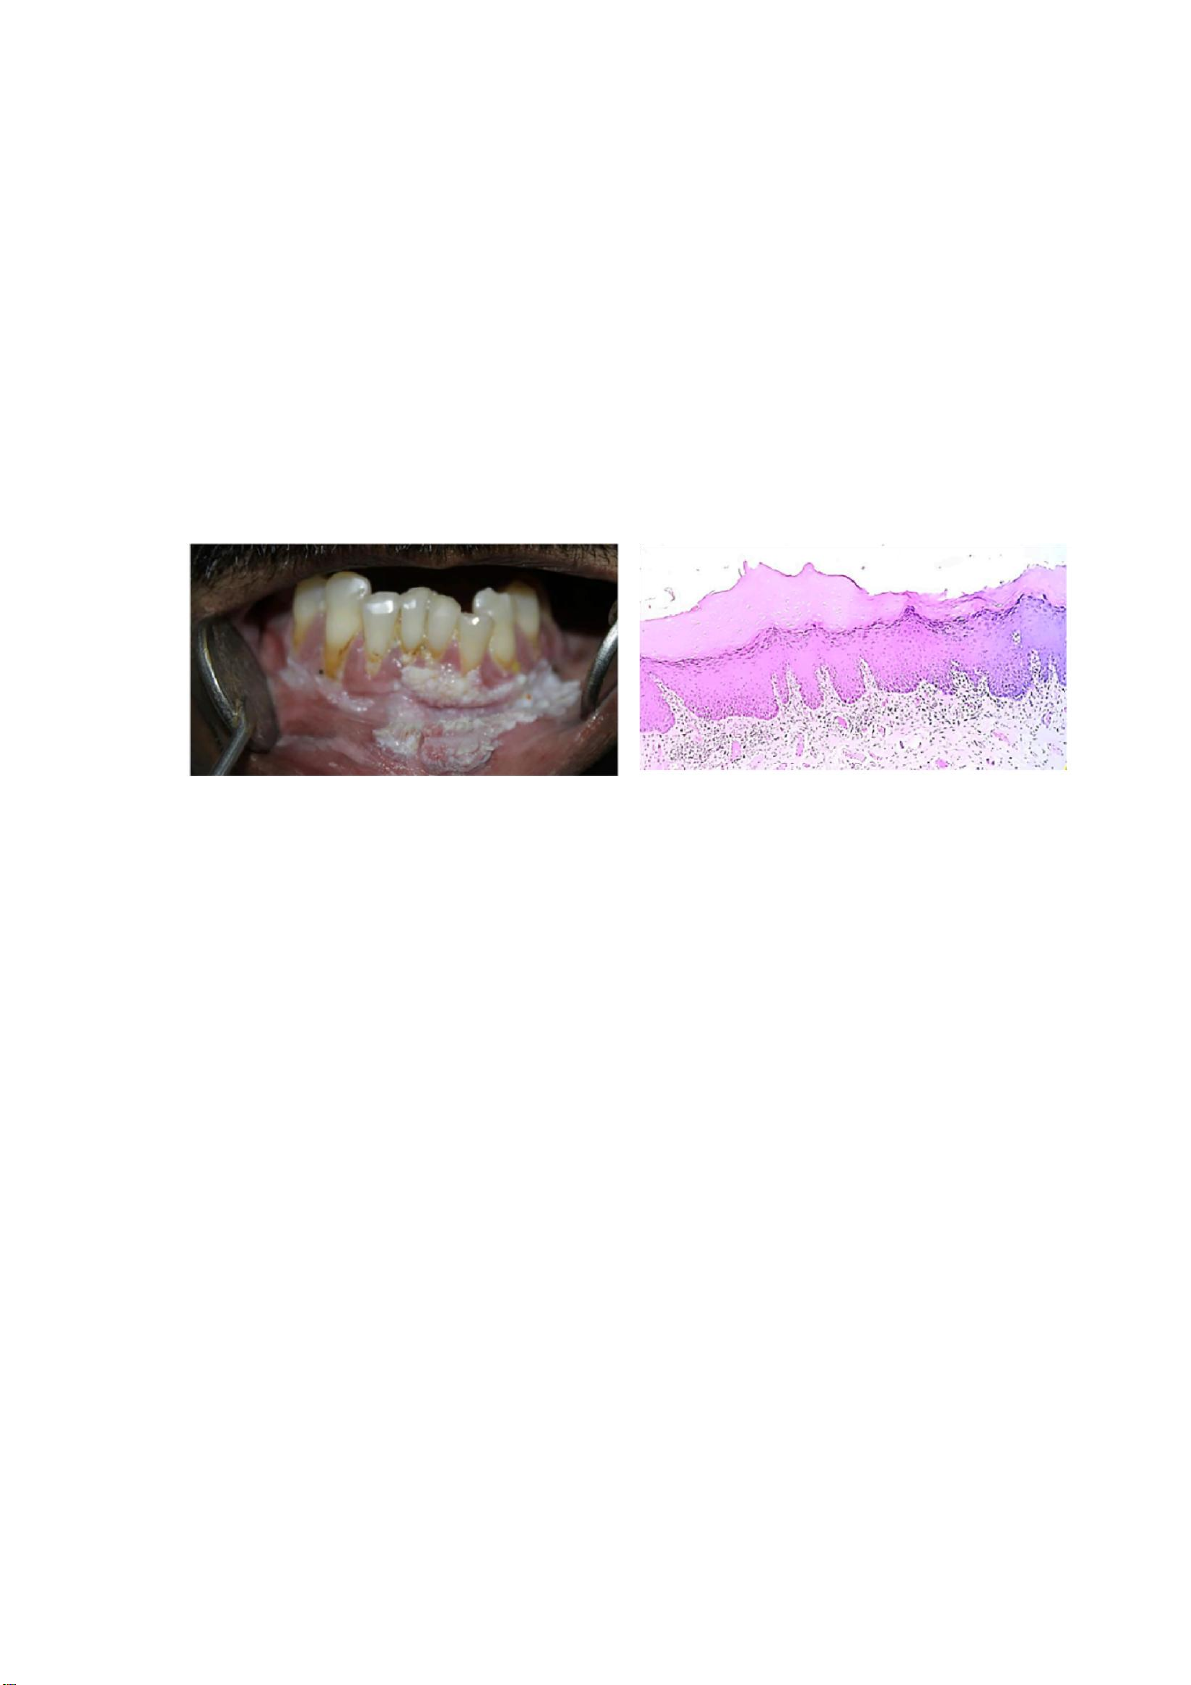

vào nhóm bạch sản không đồng nhất (Bảng 4). lOMoAR cPSD| 47207367 (a) (b)

Hình 1. (a) Bạch sản trên lâm sàng; (b) Mẫu nhuộm H&E (4x) cho thấy biểu mô lát tầng tăng

sừng. Nguồn: Kumari và cộng sự, 2022 4

Các chẩn đoán mô bệnh học đối với bạch sản niêm mạc miệng có thể là tăng sinh biểu

mô đơn thuần kèm tăng cận sừng hoặc tăng trực sừng, hoặc loạn sản biểu mô ở các mức

độ khác nhau. Thông thường, bác sĩ giải phẫu bệnh sẽ xác nhận kết quả mô học có tương

thích với chẩn đoán lâm sàng là bạch sản hay không, chỉ ra có loạn sản hay không và ở

mức độ nào. Để đảm bảo tính thống nhất khi báo cáo, khuyến cáo báo cáo giải phẫu

bệnh cần nêu rõ “sừng hóa không có loạn sản/loạn sản nhẹ/vừa/nặng, phù hợp với bạch

sản niêm mạc miệng”. Nếu chẩn đoán không kèm theo sinh thiết phải nêu rõ là chẩn

đoán chỉ dựa trên đặc điểm lâm sàng, không có chẩn đoán xác định bằng mô bệnh học.